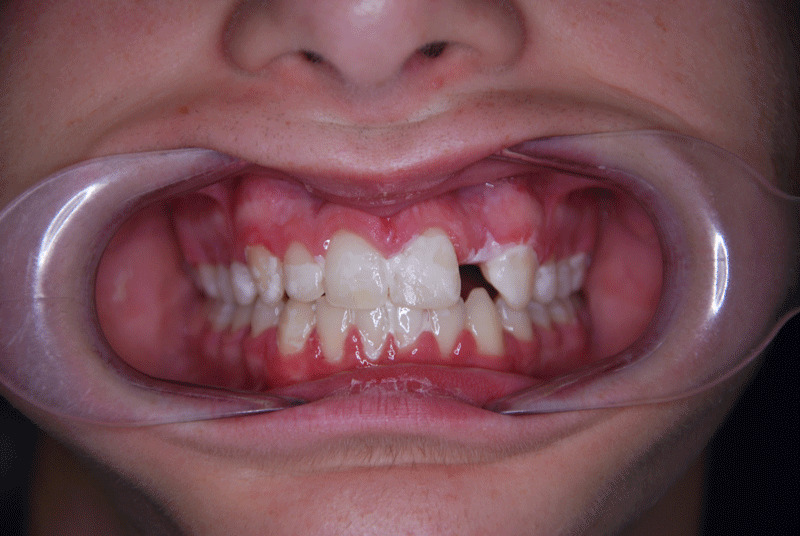

Overbite before and after

In children, deep bite is corrected with interceptive orthodontics. To avoid excessive wear, it is ideal to start treatment between approximately five and nine years of age.  Fixed orthodontic treatment is performed to correct it during adolescence, since at that age it is too late for an interceptive treatment option.

On the other hand, fixed orthodontic treatment can be performed with brackets or with transparent aligners. Particularly, in the case of brackets, these can be aesthetic or the conventional metallic ones.

To correct the overbite, the case of the child or young person should be studied through a study to assess the type and time necessary for treatment. Therefore, whether it is interceptive or fixed orthodontics, it will depend on the degree and type of overbite and the age of the patient.